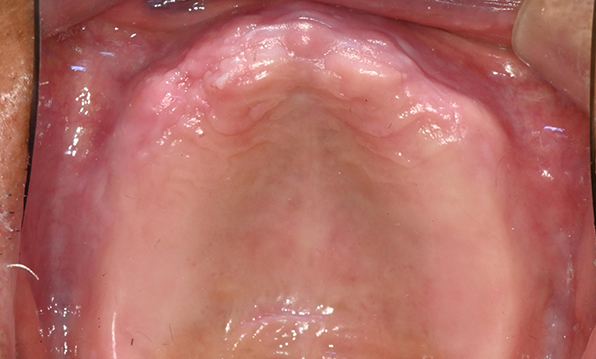

Case 01

Before After